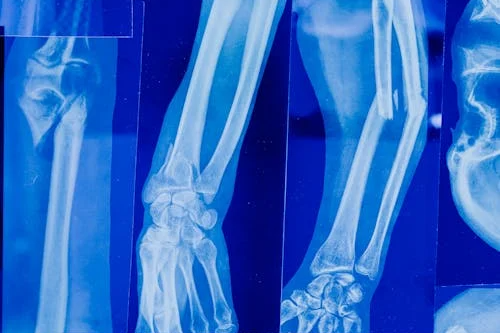

손목이 저릿저릿? 손목터널증후군 완벽 가이드!

손목이 저릿저릿? 손목터널증후군 완벽 가이드!컴퓨터를 오래 사용하거나 스마트폰을 자주 보는 현대인들에게 손목터널증후군(수근관증후군, Carpal Tunnel Syndrome, CTS)이 흔하게 발생하고 있습니